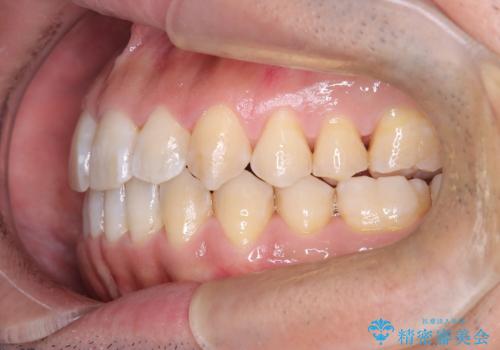

- 左上の八重歯を気にされて来院されました。精密な検査の結果、歯列全体を広げながら八重歯を奥へ移動させることで、美しい歯並びと機能的な咬み合わせが得られると診断。患者様のご希望に合わせ、透明で目立ちにくい**インビザライン(マウスピース矯正)**による治療計画を立案しました。抜歯を避け、歯を少しずつ遠心(奥)へ移動させることで、歯が並ぶスペースを確保し、叢生(歯のデコボコ)を改善します。

今回の矯正治療では、透明なマウスピース型の装置インビザラインを使用しました。この装置は目立ちにくく、取り外しが可能なため、食事や歯磨きも普段通りに行えます。遠心移動という方法で奥歯を後方に動かし、前歯を並べるためのスペースを確保。これにより、抜歯することなく、左上の八重歯を含む叢生を効果的に改善し、整った美しい歯並びと良好な咬み合わせを獲得していただけました。